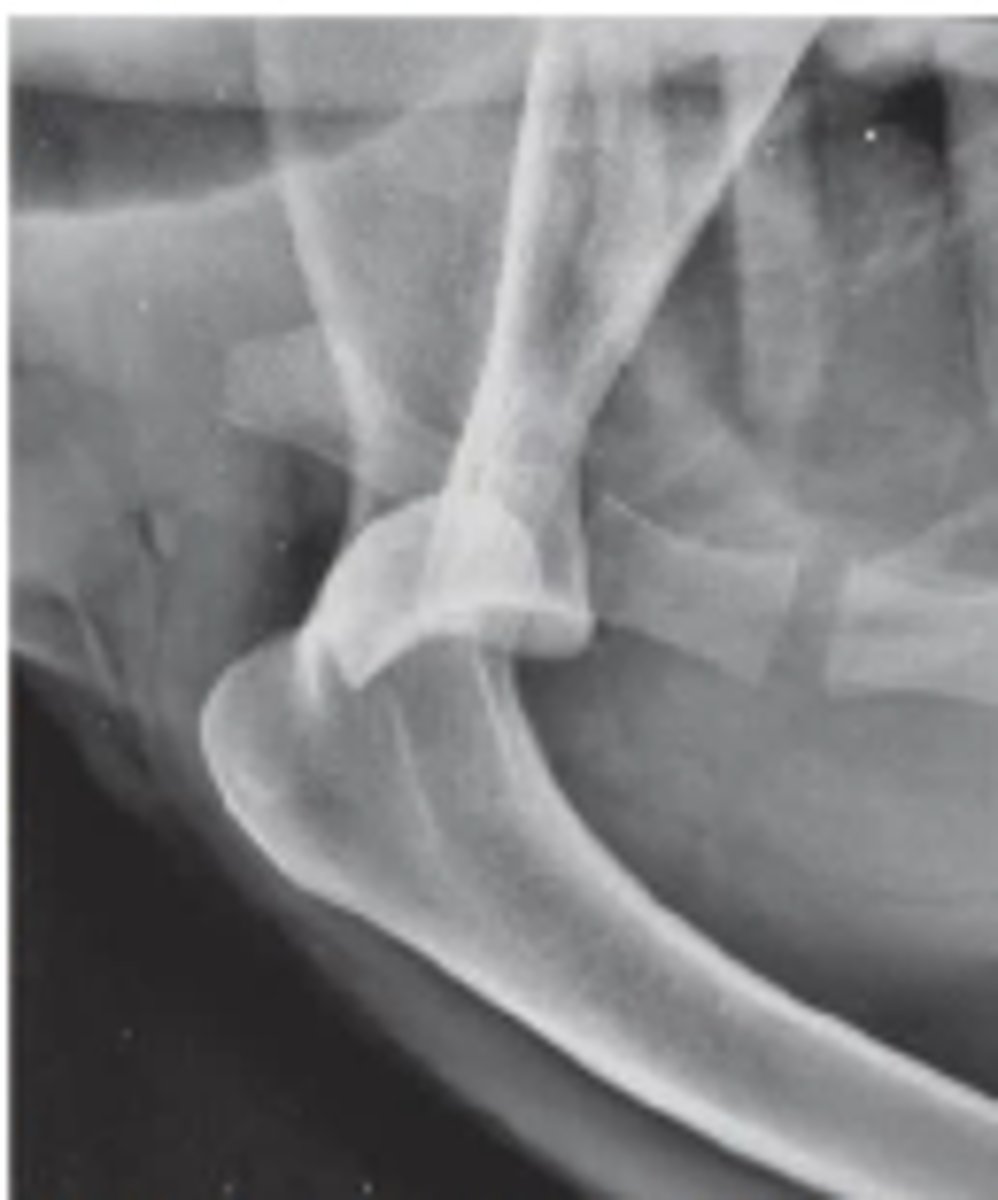

Describe a medial shoulder luxation due to trauma

unusual position of humeral head compared to glenoid cavity of the scapula

-Humeral head has been displaced medially